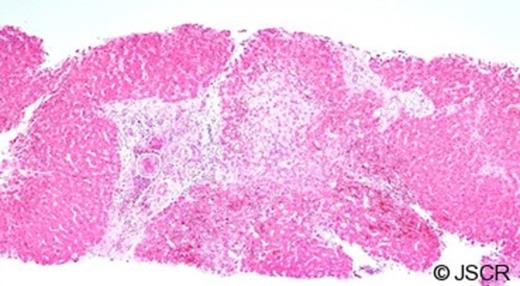

Over the next 48 hours vasopressors were weaned and he was extubated. One further short episode of wheeze was effectively managed and he was transferred to the ward. Biopsies showed irregular liver architecture with fibrosis indicating a chronic process (Figure 3). Higher magnification identified a parasite (a hydatid protoscolex) within a hepatic venule (Figures 4&5) and a diagnosis of hydatid disease (Echinococcus granulosus) was made. He was treated with albendazole 400mg bd and discharged home on day 16.

A liver biopsy showing fibrotic change within and outside the portal tracts. Note the organism further magnified in Figures 4&5.